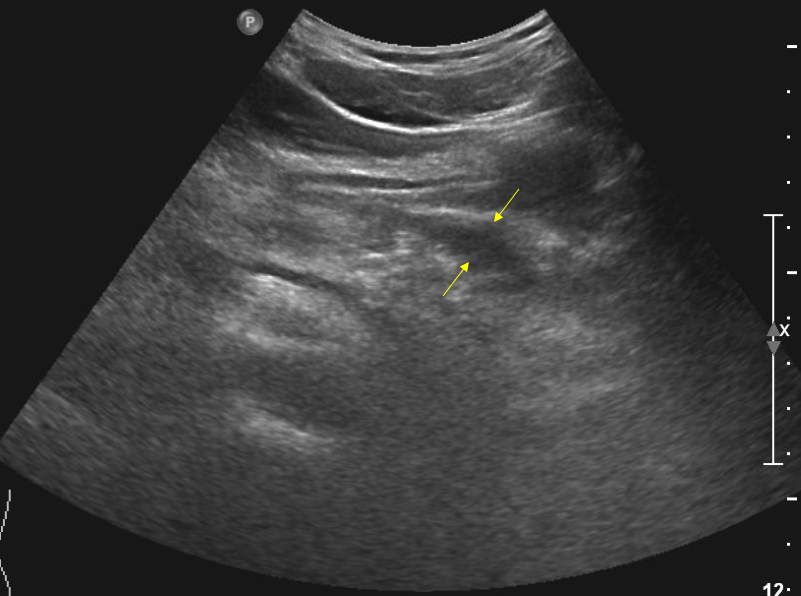

"이 사진은 환자의 상복부(배꼽을 중심으로 위쪽) 중앙을 transverse scan(옆으로 자른) 한 사진입니다. 혹시 이상 소견이 보이나요?"

자른 위치로 봐서는 췌장을 중심으로 잡은 것 같은데 당시 초음파 장비의 성능도 형편없는 데다 비만한 서양 환자의 배를 그어 놓은 사진이라 제대로 된 해부학적 landmark(길잡이가 되어줄 구조물)도 전혀 안 보여 뭐가 뭔지 도무지 알 수가 없었다.

"급성췌장염이 의심되는 환자에서 췌장이 잘 안 보이거나 보이더라도 특별한 이상 소견을 발견할 수 없을 때 우리가 찾아야 할 것은 바로 이 나비입니다." 하면서 그는 췌장으로 추정되는 희미한 구조물 바로 앞에 있는 적은 양의 'fluid shadow, 액상 음영'을 가리켰다.

Pancreas pseudocyst.png 필자가 경험한 그와 유사한 케이스